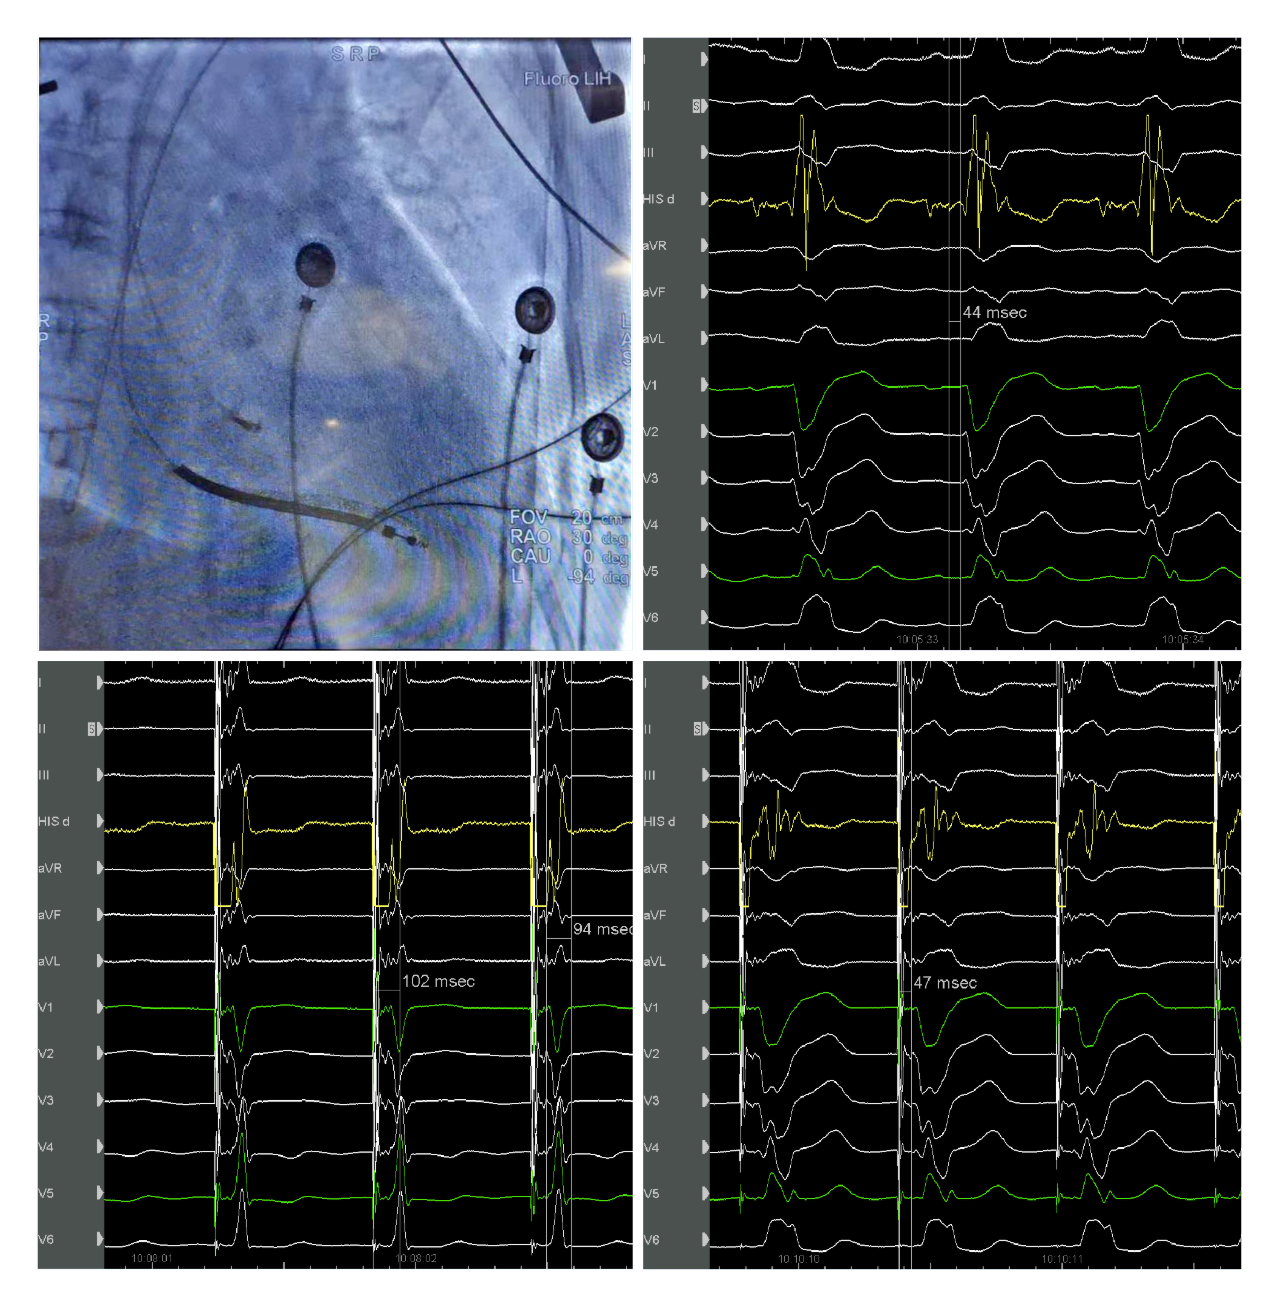

我院起搏团队演示了一例左束支起搏纠正完全性左束支阻滞用于治疗经典CRT适应症的病例。该患者为女性, 69岁,诊断:扩张型心肌病,完全性左束支传导阻滞,心功能III级,心电图显示经典完全性左束支阻滞图形,QRS193ms,心超LVD 73mm,EF 30%,符合CRTD适应症。术中顺利穿刺左侧腋静脉,在C315鞘管导引下3830电极标记到HIS电位,高电压起搏可纠正左束支阻滞,但纠正阈值较高8V/1.5ms。

(上图左上为希氏束的影像位置;右上为希氏束电位图;右下为低电压选择性希氏束起搏波型与自身一致;左下为高电压8V/1.5ms希氏束起搏纠正完左)

随后3830导线往心尖方向前移1cm拧入,同时监测起搏图形及单极阻抗,到位后起搏心电图显示不完全性右束支阻滞图形,左束支阻滞消失,测量V5导联左室达峰时间84ms,单双极高低电压起搏一致,提示夺获了左束支,夺获阈值0.7V/0.5ms。

(上图中左上为单极高电压起搏,右上为单极低电压起搏,左下为双极高电压起搏,右下为双极低电压起搏)